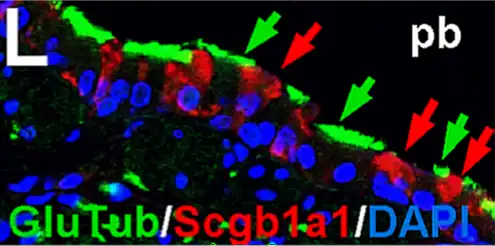

La señalización de factor de crecimiento similar a insulina (IGF en inglés), está involucrada en la homeostasis del pulmón humano. Por lo tanto, los IGF están implicados en la regeneración y reparación de heridas pulmonares en la edad adulta y, en consecuencia, se asocian con enfermedades respiratorias pulmonares relevantes como asma, fibrosis y cáncer.[12]

- ↑ a b c López I.P.; Piñeiro-Hermida S.; Pais R.S.; Torrens R.; Hoeflich A.; Pichel J.G. (2016). «Involvement of Igf1r in Bronchiolar Epithelial Regeneration: Role during Repair Kinetics after Selective Club Cell Ablation». PLoS ONE 11 (11): e0166388. doi:10.1371/journal.pone.0166388. Consultado el 6 de enero de 2021.